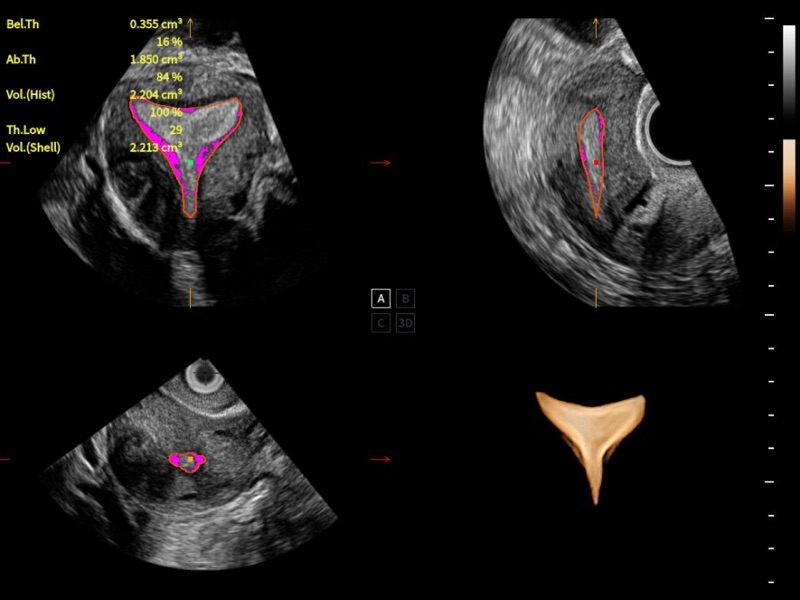

作為開(kāi)立醫(yī)療全新打造的超高端旗艦超聲產(chǎn)品,從探頭抬起喚醒開(kāi)啟掃查到多維探頭發(fā)射接收,通過(guò)先進(jìn)的場(chǎng)成像發(fā)射、自適應(yīng)聚合重建等技術(shù),基于RF Data原始射頻數(shù)據(jù)在圖像生成、高端功能等方面實(shí)現(xiàn)突破,為婦產(chǎn)科、兒科提供全方位臨床解決方案。

獨(dú)有場(chǎng)成像發(fā)射技術(shù)

自適應(yīng)聚合重建技術(shù)

獨(dú)家XPUs混合硬件架構(gòu)